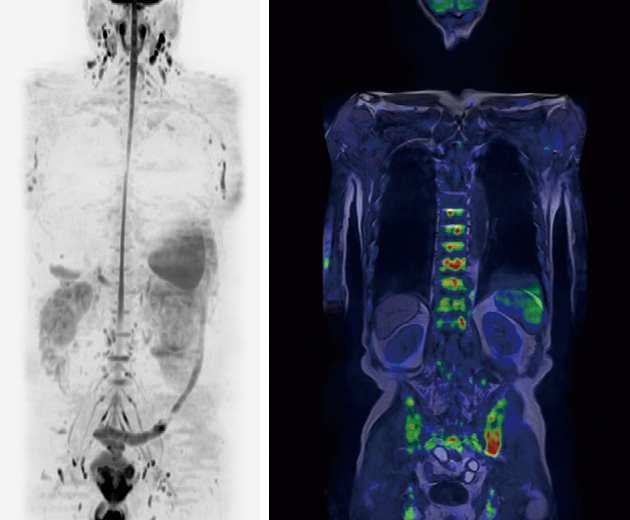

全身MRIがん検査(DWI法)は、悪性腫瘍の細胞密度が高い(細胞と細胞の間が狭い)ことに着目し、拡散強調像という撮影方法を用いて細胞間の水の動きをもとに悪性腫瘍を探索します。頚部から骨盤までの広範囲を1回のスキャニングで済む検査です。人間ドックの部位別検査にプラスしてこの検査を行うことでより精度が高くなり、がん発見率が向上します。

PET-CT検査との比較

| 全身MRIがん検査 | PET-CT検査 ※1 | |

|---|---|---|

| 薬剤 | なし | 検査薬を注射 |

| 被ばく | なし | 検査薬とCT検査の二重被ばく |

| 検査時間 | 30分程度(撮影時間 約20分) | 注射含め3時間程度 |

| 検査後の処置 | なし(すぐに帰宅可) | 放射能が下がるまで待機 |

| 検査の制限 | MRIを受けられない方 ※2 | 糖尿病・腎不全の方は、検査できない場合がある |